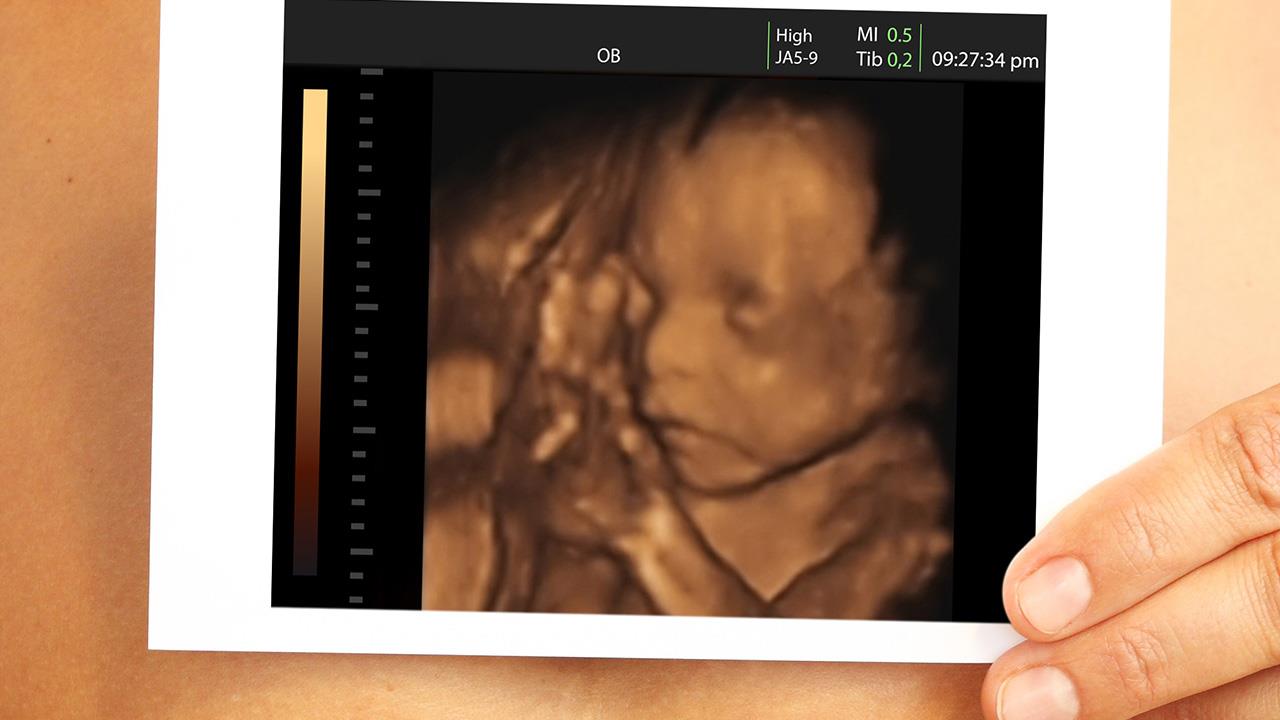

Είκοσι λεπτά μετά τη λήψη της κάψουλας, οι ερευνητές του Durham University τις υπέβαλαν στην εξέταση εστιάζοντας στην έκφραση του προσώπου των εμβρύων.

Μωρά των οποίων η μητέρα είχε καταναλώσει καρότο είχαν περισσότερες ανταποκρίσεις γέλιου στο πρόσωπο ενώ με το λάχανο είχαν περισσότερο ‘’κλαμένο πρόσωπο’’, έδειξε η έρευνα.

Οι αντιδράσεις στο πρόσωπο των μωρών συγκρίθηκαν με ομάδα ελέγχου που δεν εκτέθηκε σε κάποιον από τους παράγοντες.

Οι μητέρες έκαναν υπερηχογράφημα στις 32 και 36 εβδομάδες κύησης.